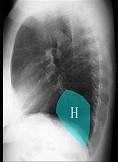

问题 如图所示正常胸部X线影像图像上,该英文字母所代表的肺段为 ( )

选项 A.H代表内基底段 B.H代表前基底段 C.H代表外基底段 D.H代表后基底段 E.H代表背段

答案 C